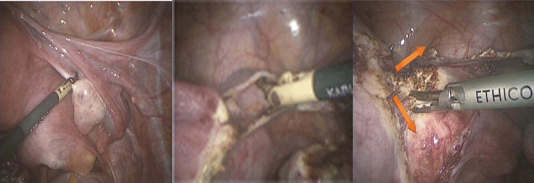

Bước 3: Cắt TC qua nội soi:

- Thì 1: Đốt và cắt dây chằng tròn, phần phụ:

+ TC được đẩy sang bên đối diện, dùng kẹp lưỡng cực đốt cầm máu và cắt dây chằng tròn cách tử cung 2-3 cm. Mở lá trước dây chằng rộng đi xuống đi phía dưới đến tận phúc mạc di động của eo TC. Đôi khi có mạch máu nhỏ, có thể cầm máu bằng dao lưỡng cực.

+ Nếu cắt phần phụ, dùng dao điện lưỡng cực cầm máu cuống mạch thắt lưng – buồng trứng và cắt bằng kéo. Nếu bảo tồn hai phần phụ, cắt cuống mạch buồng trứng-tử cung, cần cầm máu cẩn thận trước khi cắt. Sau khi cắt phần phụ bên này thì chuyển sang cắt phần phụ bên kia.

- Thì 2: Bóc tách phúc mạc bàng quang-tử cung:

+ Người phụ đẩy TC lên cao tối đa và hướng ra sau, dùng kẹp nâng mép phúc mạc lên, có thể thấy 3 thành phần mô liên kết.

+ Dùng Bipolar đốt và cắt pillar thì bàng quang có thể bóc tách xuống dưới khỏi trên âm đạo dễ dàng, và niệu quản cũng được đẩy sang bên và ra khỏi cổ TC qua động tác đẩy bàng quang xuống dưới.

- Thì 3: Đốt và cắt cuống mạch tử cung:

+ Bóc tách để bộc lộ cuống mạch TC đến mức rõ nhất, nhận biết động mạch và tĩnh mạch TC, dùng dao lưỡng cực để cầm máu cuống mạch.

- Thì 4: Đốt và cắt dây chằng TC- cùng: Sau khi bóc tách và cắt phúc mạc ở túi cùng sau, bộc lộ dây chằng TC cùng đốt và cắt bằng dao điện lưỡng cực. Đẩy trực tràng ra xa, hoặc giải phóng gỡ dính túi cùng Douglas trước khi đốt cắt.

- Thì 5: Mở âm đạo: Trợ thủ viên đẩy các vòng cao su của van vào âm đạo để bịt kín âm đạo, tránh thoát khí CO2 ra ngoài khi PTV mở âm đạo. Thường PTV dùng dao điện đơn cực để mở cùng đồ hoặc dao lưỡng cực và kéo cắt tùy kinh nghiệm PTV

- Thì 6: Lấy tử cung và khâu mõm cắt âm đạo: Dùng kèm Pozzi kẹp cổ TC kéo căng TC xuống dưới, lần theo ngón trỏ cắt hết âm đạo phân túi cùng sau. Lấy tử cung và dùng kẹp Allis kẹp mép âm đạo. Khâu mỏm cắt bằng vicryl 0, chú ý 2 góc của mỏm cắt tại vị trí 3h và 9h.